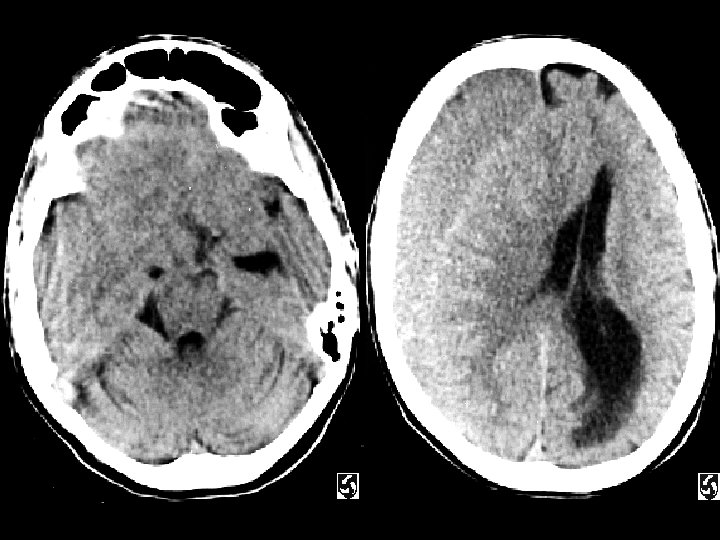

Anoxic Brain Injury Findings Hypodense cerebral hemispheres with

Anoxic Brain Injury • Findings: – Hypodense cerebral hemispheres with effacement of cortical gyri – Relative sparing of cerrebellum • Due to global insult: – Profound hypotension – Carbon monoxide poisoning • MRI findings: – Dense basal ganglia